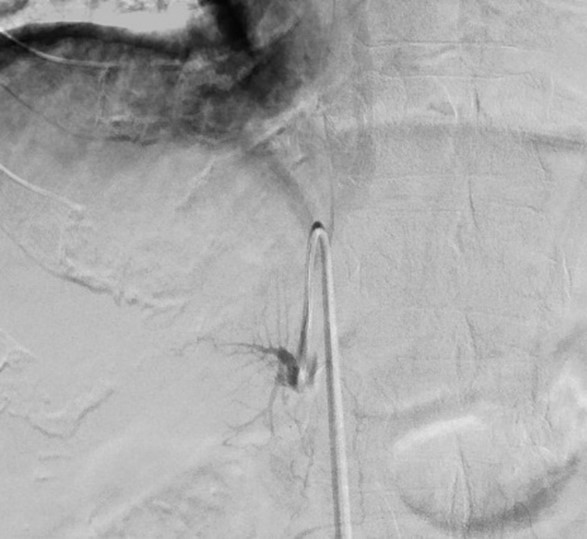

Ein weitgehend neues, alternatives Verfahren stellt die Prostataarterienembolisation (PAE) dar. Hier wird in lokaler Betäubung ein Katheter über eine Leistenarterie bis in die Prostataarterien vorgeführt. Unter Bildsteuerung werden diese unter Kontrastmittelgabe identifiziert und anschließend unter Einsatz partikulärer Embolisate verschlossen. Durch unterbundene Blutzufuhr nimmt die Größe der Prostata in den folgenden Wochen ab und die Symptome werden hierdurch gelindert.